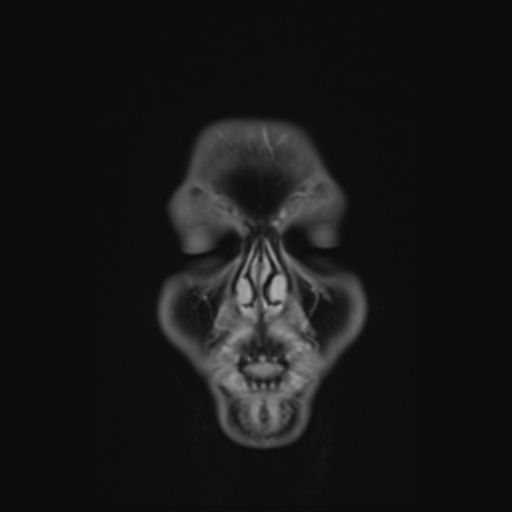

Identificativo:

Descrizione Serie: AAHead_Scout_MPR_cor